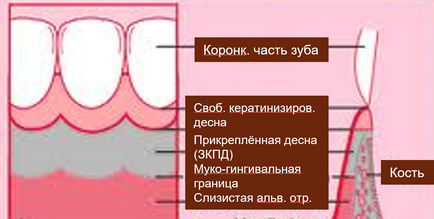

Egy másik fontos fogalom, amelyek ismerete szükséges a podiatrist. Ez a biotípus íny - ez határozza meg a vastagsága és az építészet határ gumik és csatahajók.

Megkülönböztetni 3 típusú biotípusa:

vékony biotípus

A legtöbb „kedvezőtlen” és a „kellemetlen” annak a ténynek köszönhető, hogy az ilyen típusú vastag kötőszöveti komponens a legkisebb csatahajók és epiteliális legnagyobb. Ezen kívül, valójában, vizuálisan vékony íny, hosszúkás - mutatott interdentális papillák. Protézisek legnagyobb kockázatot a recesszió a legkisebb sérülések és szemölcsök, az Advent a „fekete háromszög”. Ez a típus lehet meghatározni a beteg akkor is, ha ő állt az ajtóban - általában ez - aszténiás típusú, háromszög alakú arc.

vastag biotípus

Ünnep. Csak egy ünnep műtét és ortopédia. Összeköt gazdag réteg viszonylag Csak észrevehető epithelialis komponens SB. Tompa interdentális papilla. Kis kockázat a recesszió és a „elszabadult” szemölcsök. Általános szabály, kerek arcú termetes szögletes fogak hypersthenics férfiak - a boldog tulajdonosai biotípus.

vegyes biotípus

A név magáért beszél. Gyakori, általában együtt egy szűk elszarusodott íny. Normostenik - gyakori nyertesei biotípus.

„Prikreplonka” - mi ez és miért nem elég?

Általában ZKPD a fogak körül szélessége tartományok 4-9 mm. Mérjük meg a szélessége ZKPD nem nehéz. Először is, a szélessége mentén mérik elszarusodó fogíny vagy a „fehér csíkos” a mukogingivalnoy határt. Ezután sulkusa mért mélység és kivonjuk a teljes szélességben. Így megkapjuk a szélessége elszarusodott feszes íny.

Van egy kapcsolat ZKPD szélessége biotípus gumik. Gyakran előfordul, hogy amikor egy vastag biotípusa széles ZKPD. Sok módszerek egyre nagyobb ZKPD, amelyet nem szabad elhanyagolni .... ésszerű határokon belül.